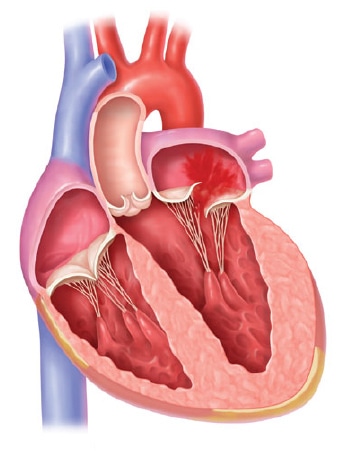

心臓は主に4つの部屋に分かれています。それぞれの部屋には、血液が逆流しないように、合計4つの扉(弁)がついています。肺で酸素化された血液は、まず左心房に集められ、次に全身へ血液を送り出すポンプ=左心室に充填されます。これら左心房、左心室の間に存在するのが、僧帽弁です。僧帽弁逆流症の多くは、弁と左心室の間を結ぶひも(腱索)が一部切れたり、左心室自体が大きくなることで弁がひっぱられたり、僧帽弁のわくが拡大することで、うまく弁が閉じることができなくなり、血液が左心室から左心房へ逆流してしまうことで生じます。

僧帽弁閉鎖不全症の僧帽弁

僧帽弁の左心室側にある腱索(僧帽弁と左心室を結ぶひも)が何らかの原因で切れたり、伸びたりすることで、僧帽弁自体の合わさりが悪くなり(接合不全)、血液が左心房へ逆流する状態です。

心筋梗塞などの虚血性心臓病、拡張型心筋症などにより左心室の動きが悪くなったり、心臓自体が拡大することで、僧帽弁を結ぶひも(腱索)がひっぱられたり、僧帽弁のわくが大きくなることで、僧帽弁自体の合わさりが悪くなり(接合不全)、血液が左心房へ逆流する状態です。